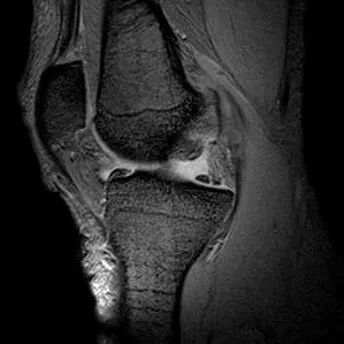

桶柄状撕裂:半月板后角增宽